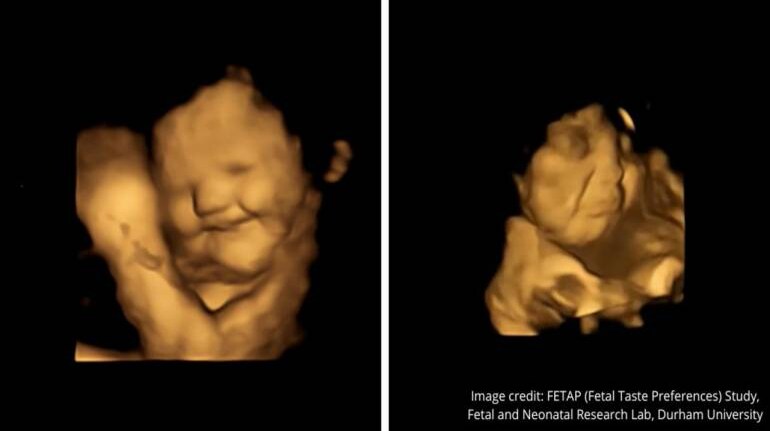

Babies in the womb are big fans of carrots but not so much leafy green vegetables -- and show it in their faces, scientists said in a new study published Thursday.

A team of scientists studied 4D ultrasound scans of 100 pregnant women and discovered that babies exposed to carrot flavours showed "laughter-face" responses.

Those exposed to kale flavours in contrast showed more "cry-face" responses.